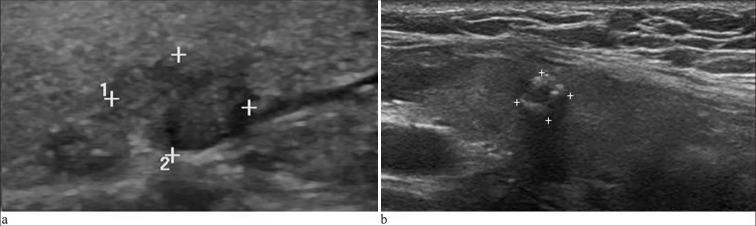

Material and methods: The clinical data of patients with thyroid nodules, suspicious of malignancy at ultrasound (US), who underwent US-guided FNAC between December 2020 and March 2023 at our cancer center were reviewed. Patients with an indeterminate diagnosis, that is, conflicting results of the BSRTC and BRAF mutation status after FNAC, were enrolled. The following four combinations of BSRTC and BRAF mutation status were considered indeterminate: (1) Group 1, BSRTC I and positive for a BRAF mutation; (2) Group 2, BSRTC II and positive for a BRAF mutation; (3) Group 3, BSRTC III and positive for a BRAF mutation; and (4) Group 4, BSRTC V and negative for a BRAF mutation. Finally, only patients who underwent surgical treatment at our center were included in the data analysis.

Results: Among the 1,044 eligible patients, 687 underwent surgical treatment. Of the 687 patients, 117 were in Group 1, 14 in Group 2, 394 in Group 3, and 162 in Group 4. Histopathological examination showed that 677 (98.5%) patients had papillary thyroid cancer, including 585 with papillary thyroid microcarcinoma, whereas only 10 (1.5%) had benign nodules. The malignancy rates were 98.3%, 100%, 98.7%, and 98.1% for Groups 1 to 4, respectively. Among the 387 patients in category 4A by the thyroid imaging reporting and data system (TI-RADS 4A) through the US, the malignancy rate was 98.4%, and for the 116 nodules <5 mm in diameter in the US, the malignancy rate was 99.1%. When combining TI-RADS 4A and a nodule diameter <5 mm, the malignancy rate was 98.9% (88/89). A total of 179 patients (26.1%) had histopathologically confirmed central cervical lymph node metastasis, and 46 (6.8%) had lateral cervical lymph node metastasis. Two nodules in Group 1, five nodules in Group 3, and three nodules in Group 4 were determined to be benign post-surgery. The benign thyroid nodules included seven dysplastic, one adenomatous, one fibrotic, and one hyperplastic.